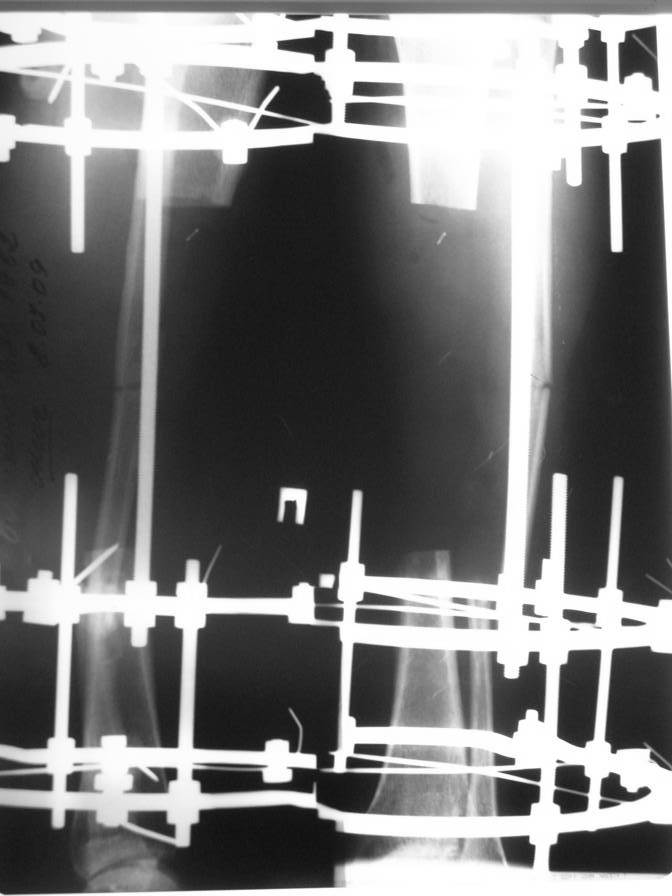

Доброго времени суток. Около двух месяцев назад я писал (http://weborto.net/forum/1247307664/) о пациенте с открытым двойным переломом  костей голени, которому в районной больнице производилась открытая репозиция  перелома большеберцовой кости с фиксацией металлической пластиной.

После нагноения раны  металлическая пластина удалена, в рану на большом протяжении обнажилась большеберцовая кость, больной в последующем около 2-х месяцев вёлся на скелетном вытяжении, предпринимались попытки стянуть рану на передней поверхности голени  местными тканями путём нанесения параллельных ране разрезов по боковой поверхности голени. К нам он поступил спустя три месяца после травмы с гнойной раной на передней поверхности голени, в которой  была обнажена на большом протяжении тусклая большеберцовая кость.На операции в костно-мозговом канале большеберцовой кости гной, кость тусклая. Была произведена резекция участка большеберцовой кости длиной 17 см, пластика дефекта мягких тканей переденей поверхности голени передней большеберцовой  мышцей, которой так же укрыт верхний и нижний отрезки большеберцовой кости, мышца закрыта расщеплёнными кожными лоскутами, кости голени фиксированы в аппарате Иллизарова. Послеоперационный период протекал без осложнений, все лоскуты  прижились, мелкие раны зажили рубцеванием, воспаления мягких тканей вокруг спиц нет.<br>

Недавно оперирован повторно- малоберцовая кость пересечена на уровне верхнего и нижнего отрезков  большеберцовой кости, перемещена на область дефекта большеберцовой кости, фиксирована в аппарате. Рентгенснимки и фото голени больного прилагаю.<br>

Имя     : рентген после1 операции.jpg

Тип     : image/jpeg

Размер  : 43919 байтов

Описание: отсутствует

Url     : http://weborto.net:8080/pipermail/ortho/attachments/20090926/a941c8f6/attachment-0011.jpg